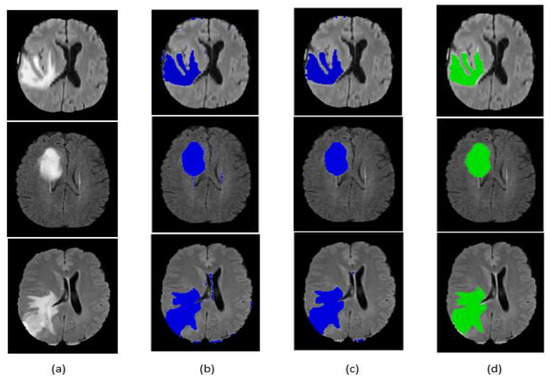

Qualitative segmentation results are presented in Figure 9 and Figure 10 for the BraTS 2017 dataset. The figures also indicate that our network is capable of accurately segmenting complete tumor regions. Our approach was tested on the FLAIR modalities for MRI images outside the BraTS 2017 dataset, and it provided good results, which guarantees the performance and power of the proposed method.

Figure 10.

Segmentation result of our method on some BraTS 2017 LGG images: (a) original image, (b) segmentation before post-processing, (c) segmentation after post-processing, (d) ground truth.